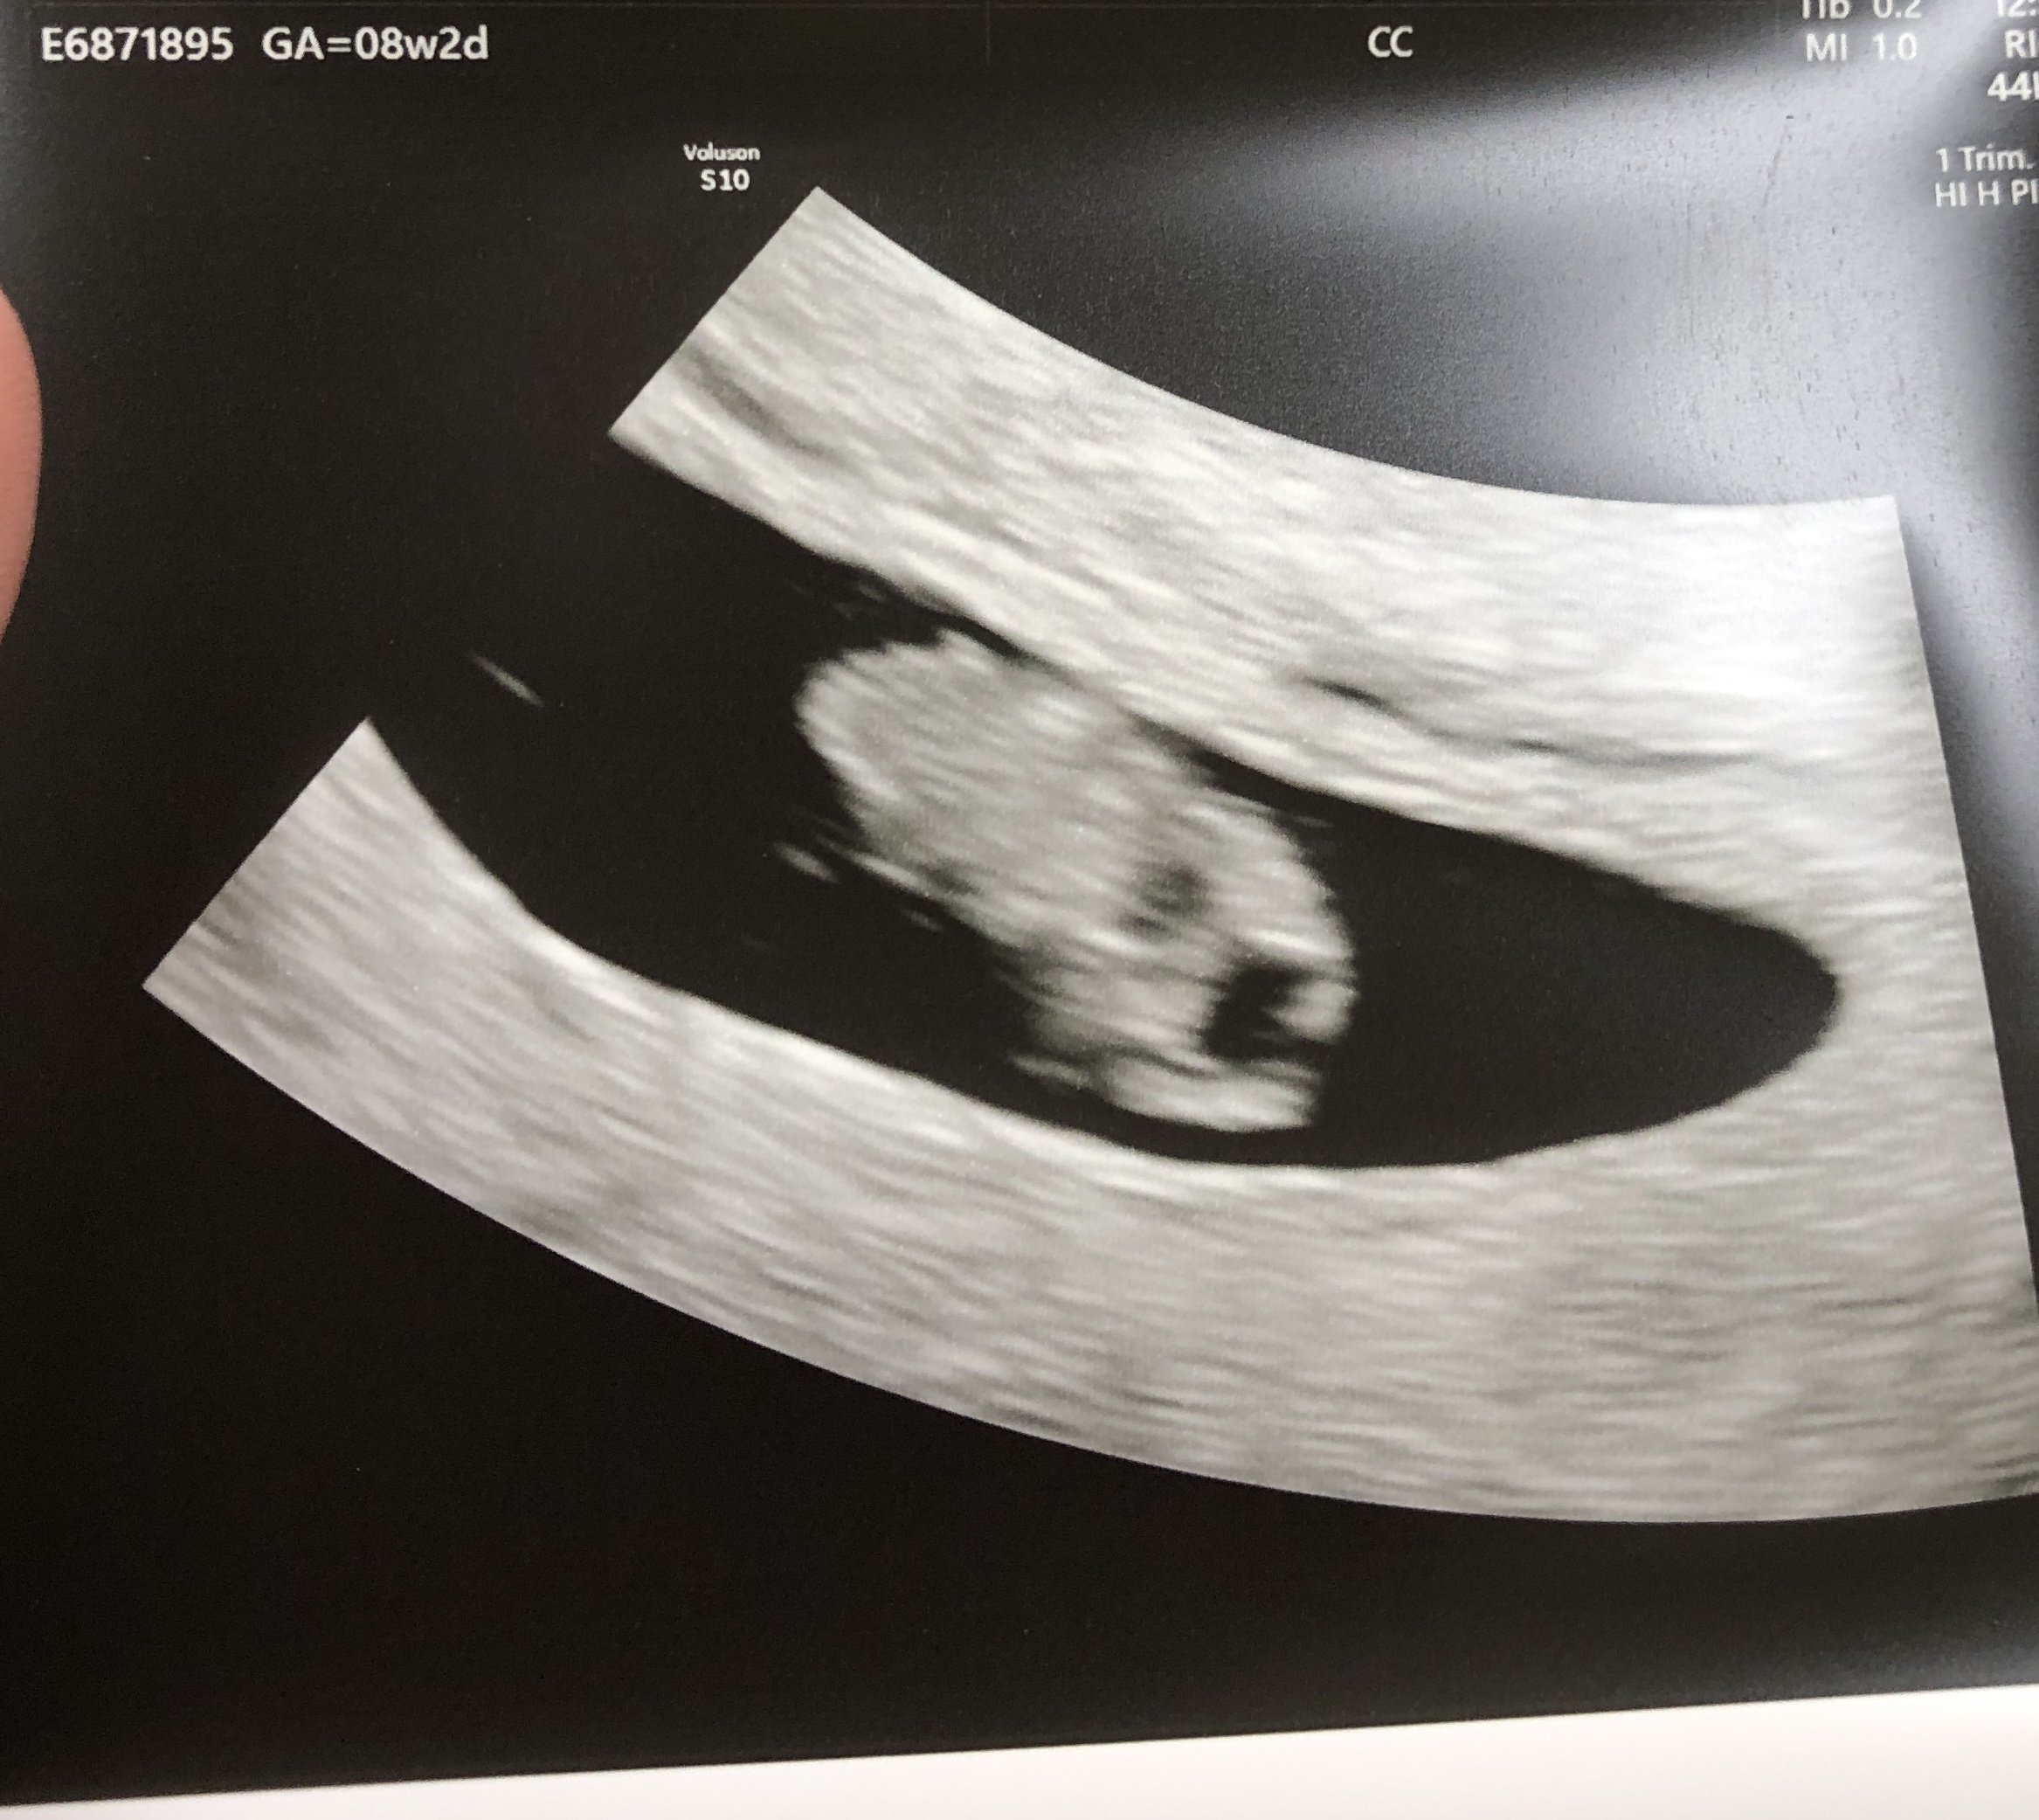

I had a little bleeding today so I went in for an ultrasound (original ultrasound appointment was scheduled for this coming Monday). Everything is good with baby, heart rate is 164 and we are right on track at 8+2. ย DD (3 yo) got her own pic which she professed was soo cute!! Turns out I have a small hemorrhage where the placenta attached. Doc said to take it easy with exercise over the next week to give it time to heal. It was very relieving to know the bleeding didnโt harm the baby!ย